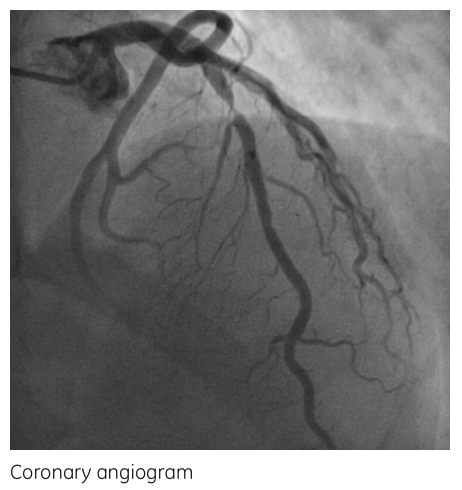

结论 该患者钙化积分为0,但是在CT影像上可以看到左前降支一处90-99%的重度狭窄(图2)。 In this patient with a calcium score of 0, a subtotalocclusion of the LAD & #40;90-99 %& #41; could be visualized on the CT images.

SPECT显示在相应的前壁有一个可逆性灌注缺损区(图3)。该患者进行了冠状动脉造影并确定诊断(图4),之后进行了支架置入术。 Correspondingly, SPECT revealed a large reversible perfusion defect in the anterior wall. The patient underwent coronary angiogramwhere the diagnosis was confirmed and stenting of the lesion was performed.

图4: 冠脉造影图像